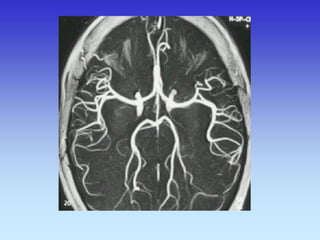

METODE PRIKAZA KRVNIH ŽILA

•UZ-DOPPLER

•DSA

•CTA

•MRA

VASKULARNA OPSKRBA WILLIS-ijev prsten

a. cerebri ant.

a. cerebri media

a. cerebri post.